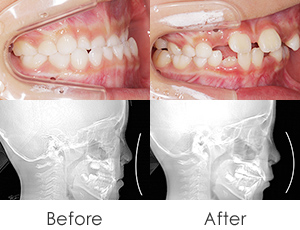

出っ歯と前歯のガタつきにお悩みだった20代女性の症例です。

金属アレルギーがあるため、メタルフリーで治療できる【インビザライン】による抜歯矯正を選択されました。

• 小臼歯4本抜歯

• インプラントアンカー(TAD)併用

• 正中のずれ・口元突出感を改善